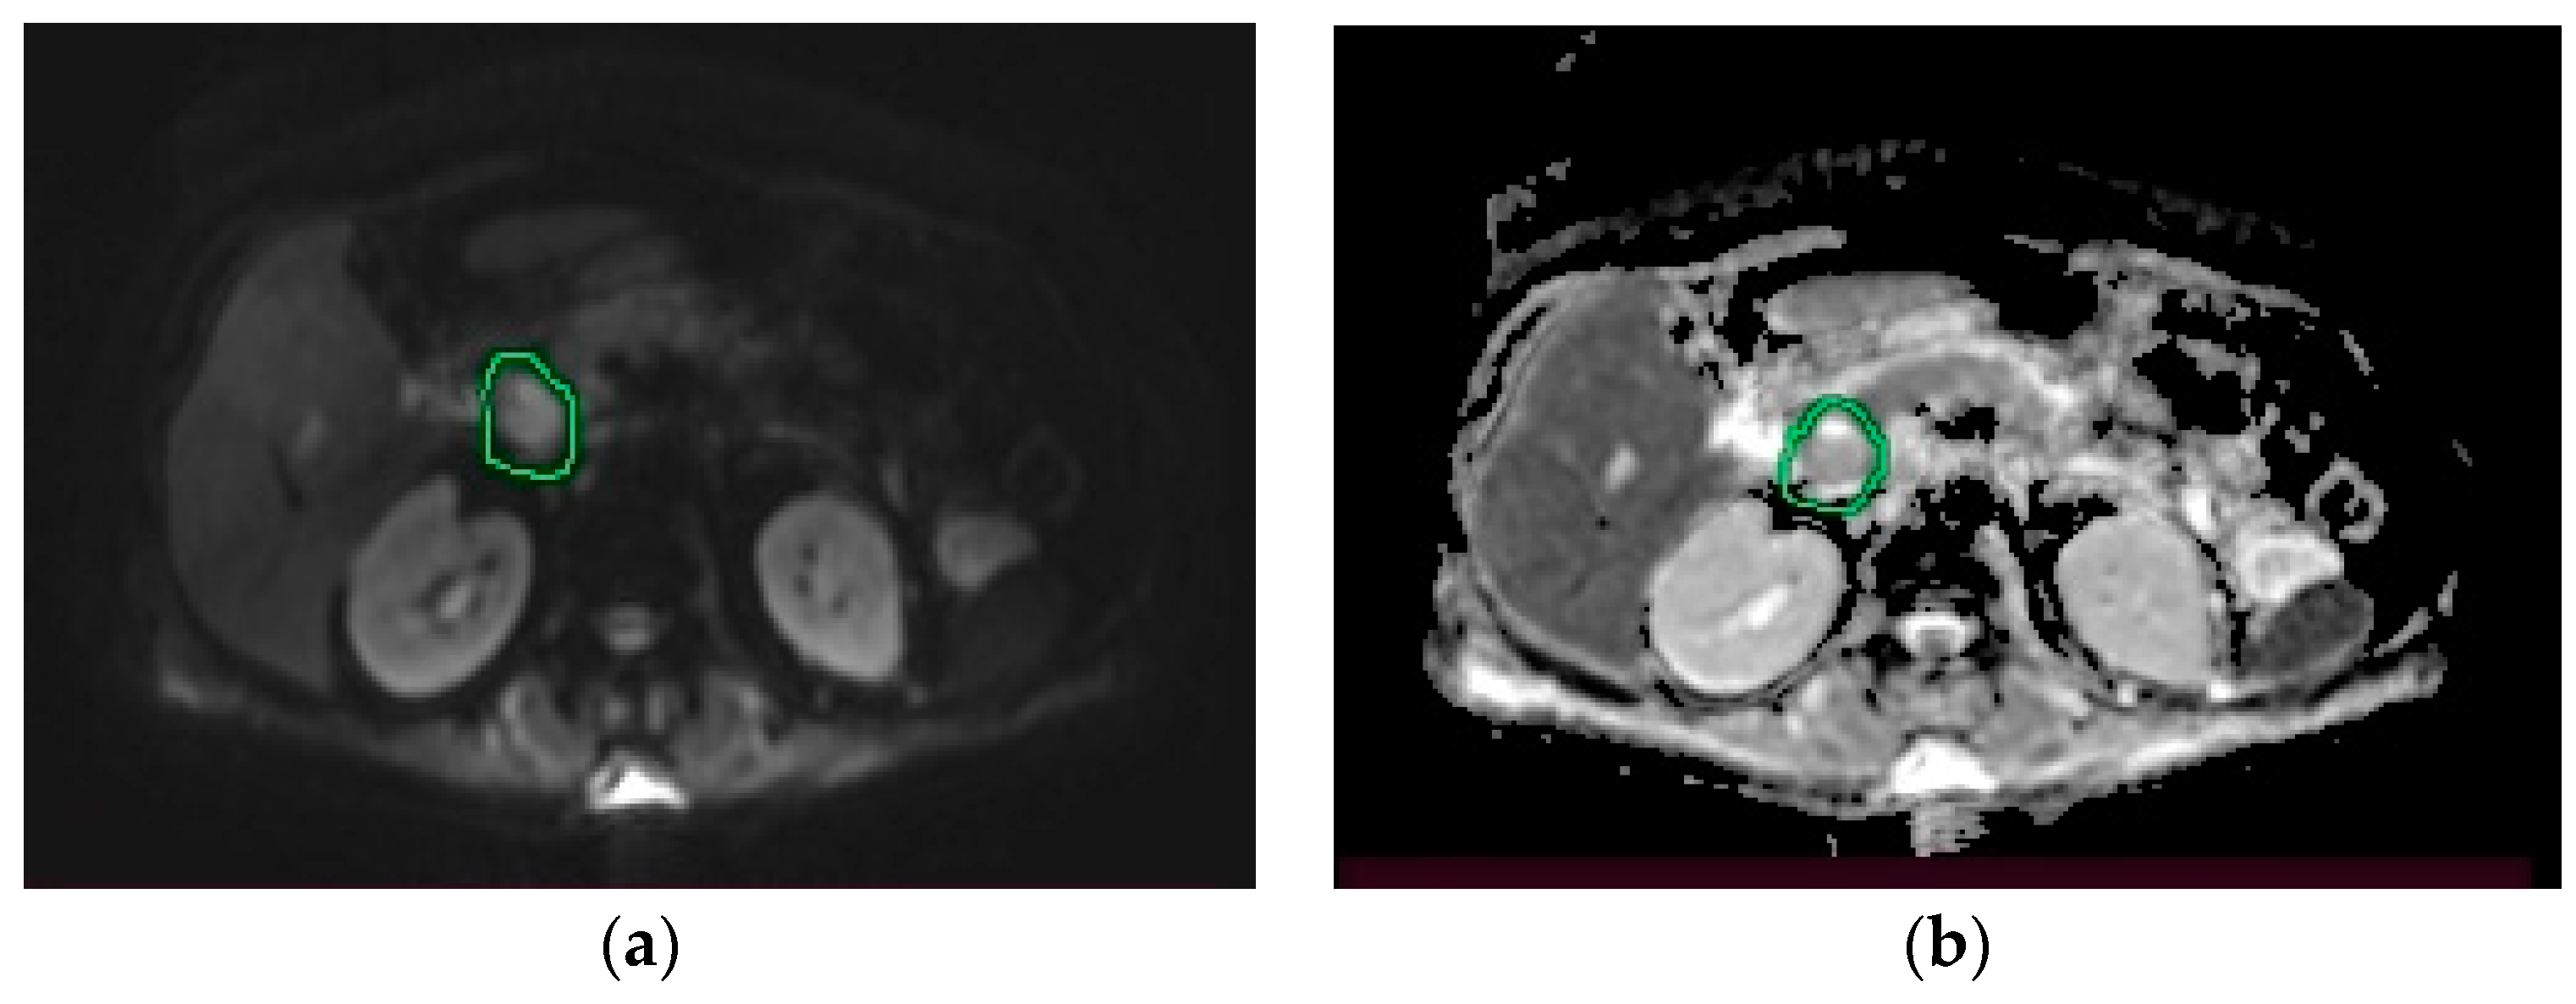

2. Case Presentation